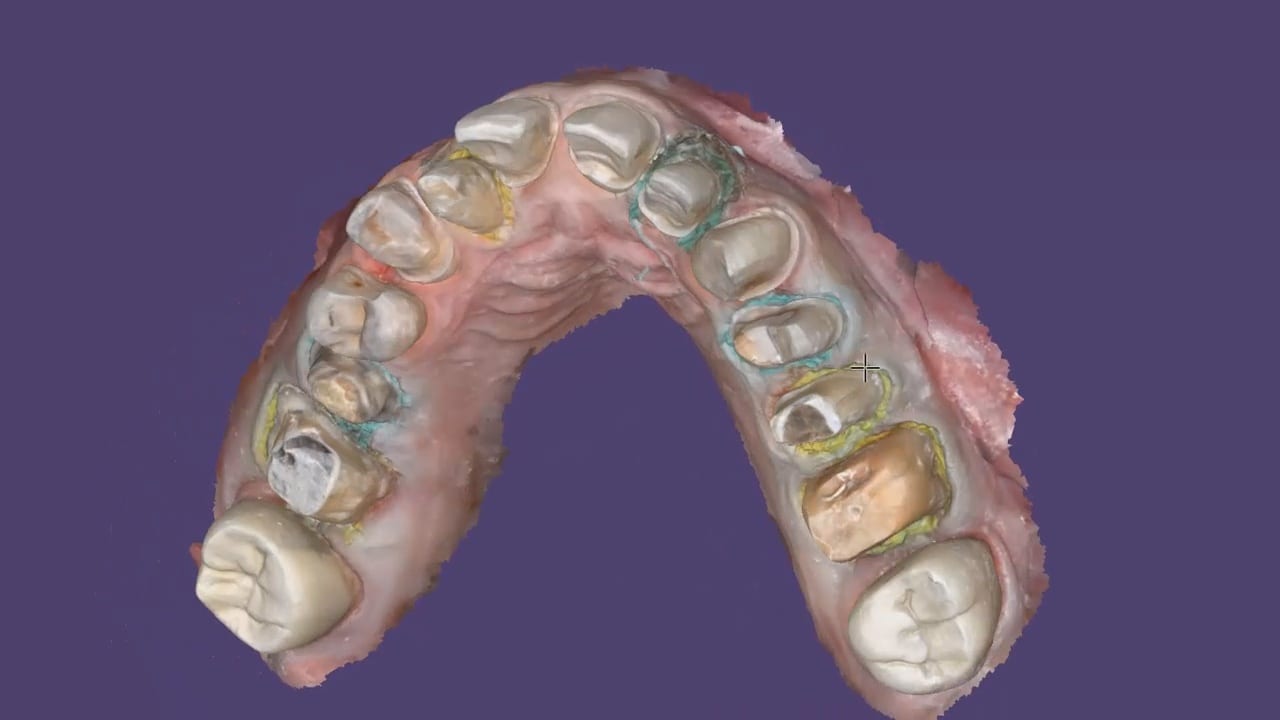

This is an advanced case and won’t make any sense unless you have taken our course on digital dentistry. If you are an advanced user, watch how we break this complex case up into many small manageable segments to create full arch impressions of multiple prepared teeth.

Take note of the fact how the buccal bite is captured over a long course of time. This indicates that the arches are related to each other properly and we have not lost track of the bite. Pay attention to how we operate “independent of time and sequence.”

segmental imaging to building a master model